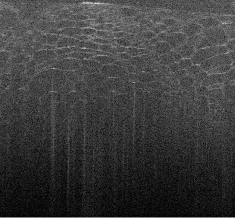

Cross sections from the samples are shown in Figure 1. This highlights the impact of dispersion compensation, and the increase in lateral resolution away from the focal plane with the ISAM method.

| IFFT | dispersion corrected | ISAM | |

|---|---|---|---|

|

beaded gel |

![]() |

cucumber |

We performed MBIR on a desktop PC, with an implementation of (2.3) written in Matlab. We ran the following on sub-sampling patterns for :